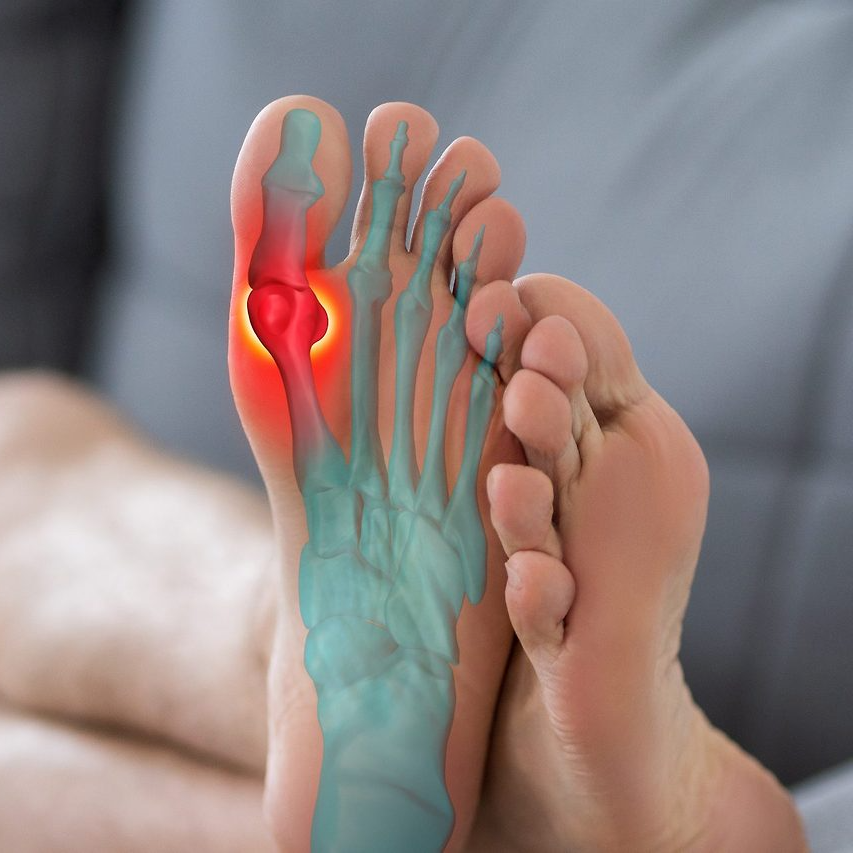

일상생활에서 가장 흔한 골절 부위 중 하나가 바로 새끼발가락이다. 작은 부위지만 벽이나 가구 모서리에 부딪히거나, 무거운 물건이 떨어지는 충격으로 쉽게 골절이 발생할 수 있다.

특히 여름철 실내에서 맨발로 다니다가 발생하는 경우가 많다. 새끼발가락은 작은 뼈이지만 보행 시 균형을 잡는 역할을 하기 때문에 골절 시 통증이 크고 생활 불편이 심하다. 증상으로는 붓기, 피멍, 통증, 변형, 체중 부하 시 통증 악화 등이 있으며, 방치할 경우 잘못 붙어 변형이 남거나 보행 시 통증이 지속될 수 있다. 골절은 단순히 ‘금이 간 정도’의 피로골절부터 뼈가 완전히 어긋나는 개방성 골절까지 다양하다.

발가락 골절은 손상 형태에 따라 몇 가지로 구분된다. 의료기관에서는 이를 영상검사로 확인한 뒤, 골절 유형에 따라 치료 및 위로금 지급액을 다르게 산정한다.